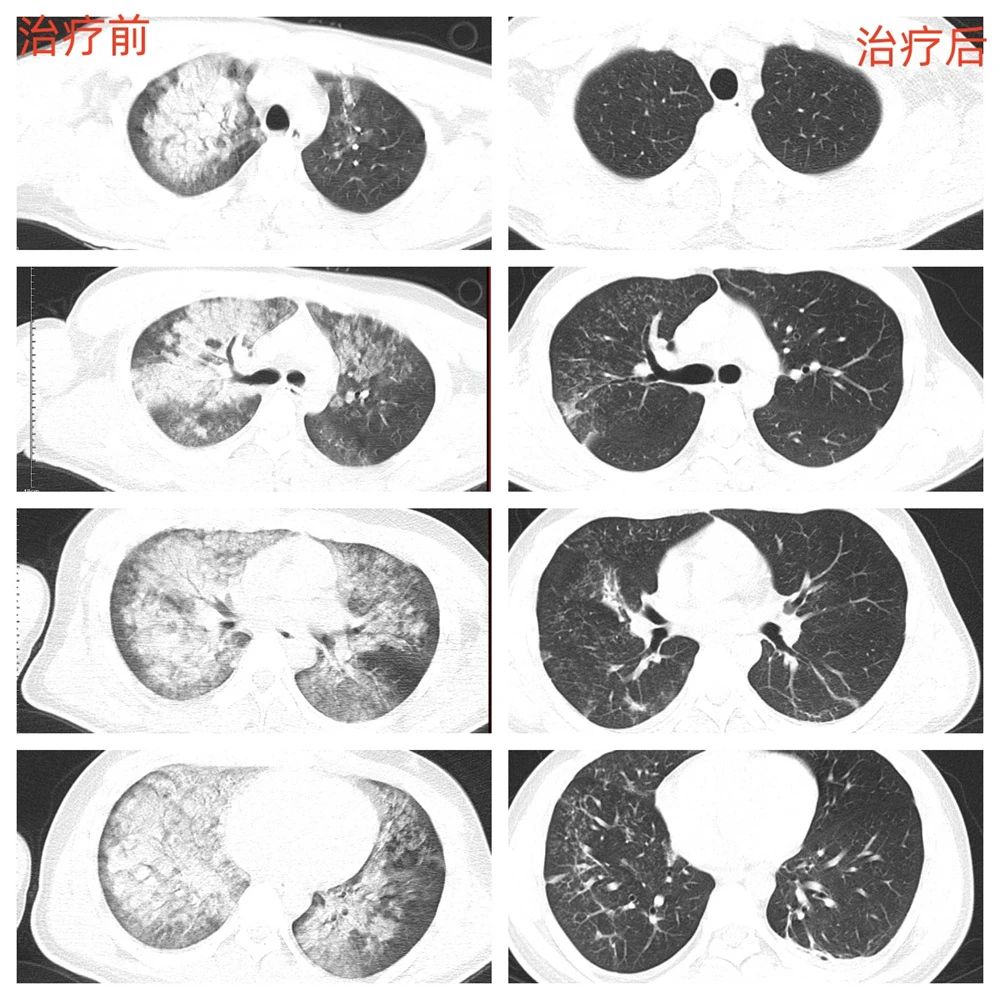

在呼吸与危重症医学科主任吴德生的指导下,治疗团队在床旁为患者实施支气管镜检查。镜下画面触目惊心:气管及各级支气管内棕褐色淤泥团块,部分亚段支气管已阻塞。医护人员屏气凝神,通过生理盐水灌洗、负压吸引等精准操作,历经50分钟将气道内异物逐一清除。术后患者氧合指数逐步上升,呼吸机参数显著下调。

两天后,第二次支气管镜治疗顺利实施。当镜端探入曾经被完全阻塞的右下叶基底段时,清晰的支气管黏膜已开始恢复正常红润色泽。这个细微的变化,让连续守护在病床旁的主治医师激动地记录:“镜下可见新生的希望!”

经过两周精心治疗,邰某不仅成功脱离呼吸机,转回呼吸与危重症医学科治疗后康复出院。出院那天,这对年轻的夫妻俩捧着锦旗,在科室的大门前和医护人员合影留念。